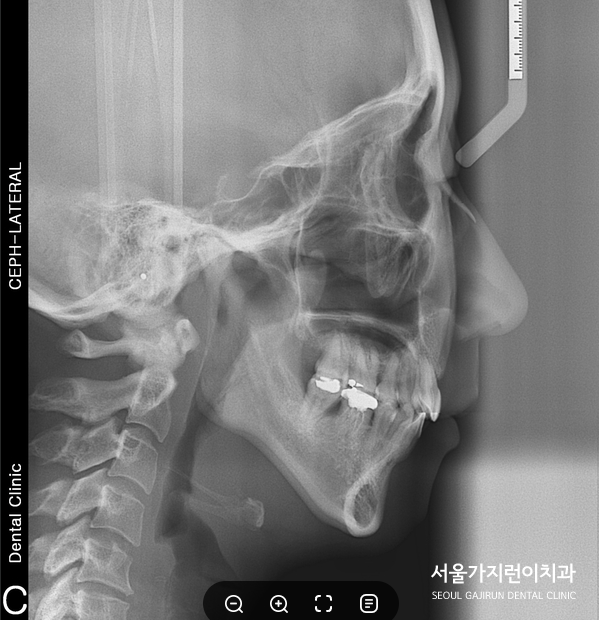

짜잔! 총 치료기간은 1년 6개월 정도 소요됐는데요. 상악 앞니의 뻐드러짐과 돌출입 개선이 되었고 불규칙적인 치열도 가지런한 배열로 완성이 되었습니다. 돌출입과 무턱 증상의 개선여부 안모 변화에도 큰 영향을 미치는데요. 하악골이 전방 및 상방으로 나와 얼굴의 길이가 짧아졌고 무턱 느낌도 개선되어 턱끝이 살아난 것을 확인할 수 있었습니다.

환자분의 경우 치료가 끝난 후 3년이 지난 시점에도 건강한 상태로 유지가 되었는데요. 치료를 마친 후에도 꾸준히 서울가지런이치과 교정과 의원에서 검진을 받아보고 계십니다.